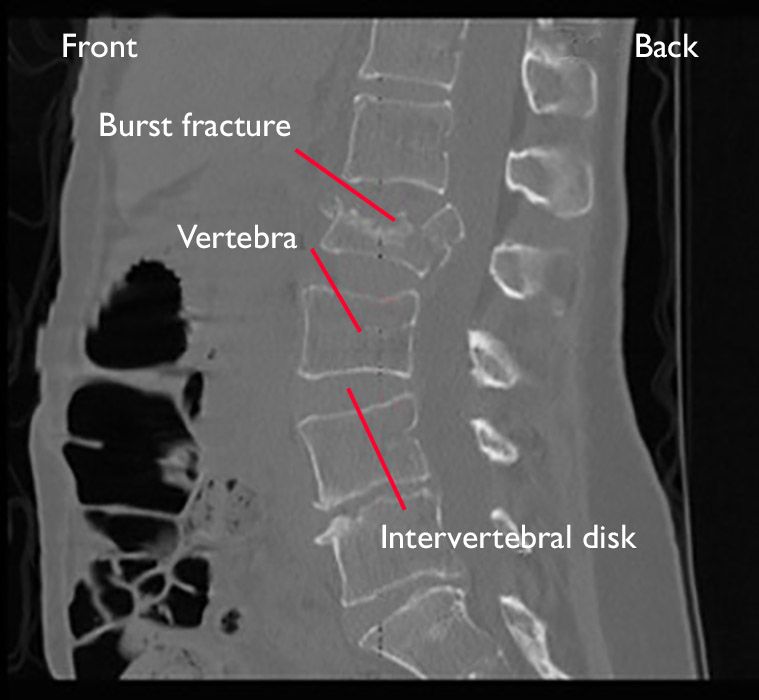

Frattura vertebrale

- Descrizione: Rottura dell'osso di una delle vertebre della Colonna vertebrale.